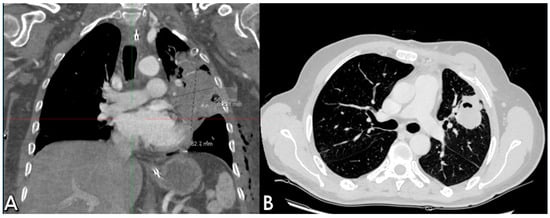

The postoperative course took place in the Intensive Care unit for nine days, during which the patient received blood transfusions (2 units), vasopressor support, antibiotic therapy and steroids. Bronchial toilet was performed twice to free of blood and secretions the tracheobronchial tree. Due to the occurrence of a fever and a rise in the inflammation markers a CT scan was ordered on p.o. day 3, showing an intraparenchymal hematoma (6 cm) in the left upper lobe (LUL), without active bleeding spots (Figure 2A). A conservative approach was chosen and the fever progressively subsided, blood tests gradually normalized and the hematoma progressively shrunk (Figure 2B). The patient returned to the ward on the 9th p.o. day and was discharged from the hospital on p.o. day 20. A chest film obtained a month later revealed almost complete reabsorption of the hematoma, with a very satisfactory lung re-expansion (Figure 3). Data regarding preoperative parameters, intraoperative steps and postoperative events are reported in Table 1.

Figure 3. 50-day p.o. chest film demonstrating almost total hematoma reabsorption, with satisfactory lung ventilation.